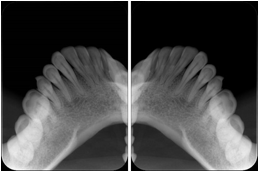

2 Occlusal Vertical Maxilla A Dental Image Layout

DL-C001A

Reference: DL-C001-U1L0

Reference: DL-C001-U2L0

00

Occlusal

18, 17, 16, 15, 14, 13, 12, 11, 13, 12, 11

01

21, 22, 23, 24, 25, 26,27, 28

2 Occlusal Vertical Mandible A Dental Image Layout

DL-C002A

Reference: DL-C002-U0L1

Reference: DL-C002A-U0L2

10

48, 48, 47, 46, 45, 44, 43, 42, 41

11

31, 32, 33, 34, 35, 36, 37, 38

2 Occlusal Horizontal Maxilla A Dental Image Layout

DL-C003A

Reference: DL-C003-U1L0

Reference: DL-C003-U2L0

18, 17, 16, 15, 14, 13, 12, 11, 13, 12, 11, 21, 22, 23, 24, 25, 26,27, 28

2 Occlusal Horizontal Mandible A Dental Image Layout

DL-C004A

Reference: DL-C004-U0L1

Reference: DL-C004-U0L2

48, 48, 47, 46, 45, 44, 43, 42, 41, 31, 32, 33, 34, 35, 36, 37, 38